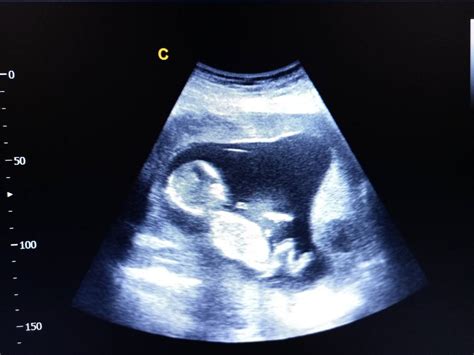

În săptămâna 33 de sarcină, bebelușul are aproximativ două kilograme și măsoară între 42 și 46 cm lungime. El continuă să crească rapid, iar creierul și plămânii se maturizează. Pielea sa devine roz, mai puțin transparentă, datorită stratului de grăsime care se acumulează sub ea, dându-i un aspect tot mai asemănător cu cel al unui nou-născut. Corpul său este aproape complet pregătit pentru viața în afara uterului.

În ceea ce privește monitorizarea sarcinii, aceasta este esențială. La 33 de săptămâni de sarcină, ecografia de trimestrul 3 sau morfologia de trimestru 3 ar trebui efectuate. Mergi la toate controalele programate, acestea vor fi mai dese acum. Vorbește cu medicul despre modalitatea de naștere și fă aranjamentele necesare. Alege maternitatea sau spitalul privat adecvat și descoperă condițiile specifice. Discută deschis cu medicul tău despre ceea ce implică o naștere naturală sau una prin cezariană.